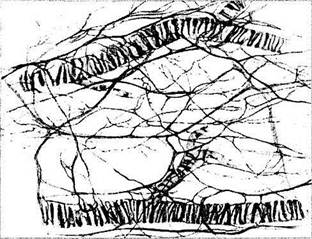

Сосуды надсосудистой пластинки и стромы сосудистой оболочки исключительно обильно снабжены как парасимпатическими, так и симпатическими нервными волокнами (рис. 3.8.58).

Рис. 3.8.58. Особенности распределения нервных волокон между сосудами сосудистой оболочки